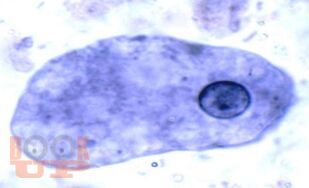

Учебное наглядное пособие «Атлас по медицинской паразитологии с экологическими основами распространения паразитозов на территории Красноярского края» рекомендуется для использования в образовательных целях для студентов 1-го курса медицинских вузов. Настоящее издание иллюстрировано схемами жизненных циклов паразитов, микрофотографиями, морфологией целого организма паразита или его частей. Атлас содержит материалы по распространению и динамике паразитозов на территории Красноярского края. Представленные материалы служат основой для самостоятельной работы студентов в альбомах для практических занятий.